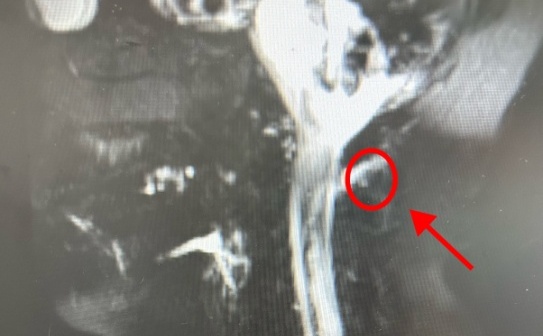

据了解,阿维曾在广东珠海的医院求医,医生说他是颈椎问题,但经过治疗都没效果。于是,他来到了广东三九脑科医院,经诊断,阿维之所以头痛是因为脑“漏水”,也就是脑脊液发生了渗漏。

好端端的,脑部怎么会“漏水”呢?医生经过了解,怀疑此次渗漏与一次急刹车有关。

原来,阿维所开的网约车有自动刹车功能。有一天,他驾车行经斑马线时,一名路人突然冲出,“车可能预警到有人要过马路,我当时没有防备,所以车很猛烈地刹了一下,我的头就往前倾了一下。”

广东三九脑科医院神经内二科主任钟水生解释,“可能有骨刺把他的硬脊膜刺破了,出现了脑脊液的渗漏。”

疼痛科副主任医师李庆华认为,林大姐的症状疑似低颅压性头痛。经检查,其颈椎处有明显的漏液。医生表示“是脑脊液漏出导致的低颅压性头痛,且破口位置较高,在颈椎处。”

“临床上,低颅压患者脊椎相应的漏液部分,经常会发现骨刺。”李庆华表示这与生活习惯有很大的关系,低头族要特别当心。